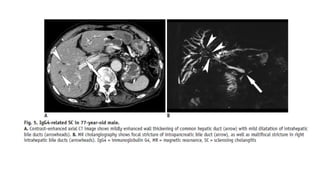

• IgG4-Related Sclerosing Cholangitis

• Immunoglobulin G4-SC is bile duct involvement of IgG4- related systemic disease (IgG4-RD) .

After the pancreas, bile ducts are the second most common organ, involved with IgG4-RD.

Patients with IgG4-SC are predominantly males in their 60s (mean age, 63 years) . Patients

with IgG4-SC commonly present with obstructive jaundice. Like other IgG4-related diseases,

the serum IgG4 is frequently elevated.

• Abdominal US has limited value for diagnosing IgG4- SC, although it may show thickening of

the bile duct and gallbladder. In cases of IgG4-SC, cross-sectional imaging, such as CT or MR

imaging, demonstrates long-segmental, symmetrical, circumferential wall thickening and

delayed contrast enhancement of the involved bile ducts

Secondary Sclerosing Cholangitis •IgG4-Related Sclerosing Cholangitis • Immunoglobulin G4-SC is bile duct involvement of IgG4- related systemic disease (IgG4-RD) . After the pancreas, bile ducts are the second most common organ, involved with IgG4-RD. Patients with IgG4-SC are predominantly males in their 60s (mean age, 63 years) . Patients with IgG4-SC commonly present with obstructive jaundice. Like other IgG4-related diseases, the serum IgG4 is frequently elevated. • Abdominal US has limited value for diagnosing IgG4- SC, although it may show thickening of the bile duct and gallbladder. In cases of IgG4-SC, cross-sectional imaging, such as CT or MR imaging, demonstrates long-segmental, symmetrical, circumferential wall thickening and delayed contrast enhancement of the involved bile ducts • Differentiation of IgG4-SC from other types of sclerosing cholangitis, especially from PSC, is clinically important as IgG4-SC shows a dramatic response to steroid therapy . Patients with PSC are generally younger and less symptomatic than those with IgG4-related disease .